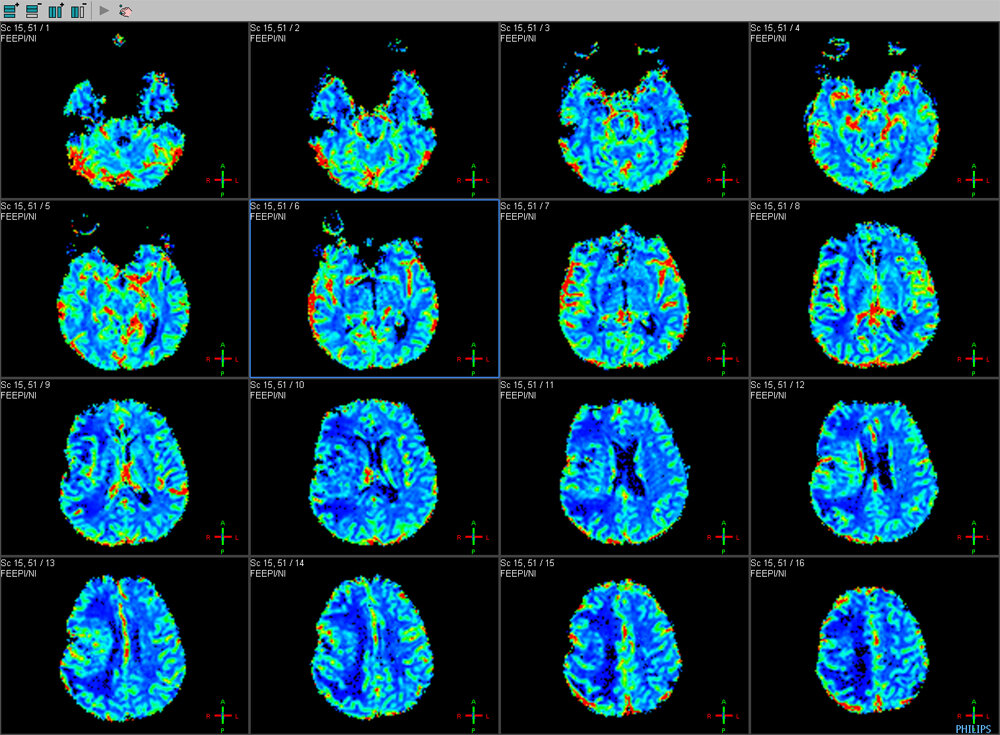

uniquerose Oluşturma zamanı: Eylül 20, 2015 Oluşturma zamanı: Eylül 20, 2015 şizofreni gerçeği şudur ki; şizofreni psikolojik bir hastalık değildir. psikoz bir bozukluktur. yani beyine dayalı ruhsal bozukluk şizofreni latincede ''erken bunama'' demektir. günümüzde yaygın olan bu bozukluğun asıl çıkış sebebi, genetiktir ya da çevreyle alakalı bir durum, aşırı bağımlılık vaya aşırı korkularda buna sebep olabilir. GENETİK OLARAK NASIL ORTAYA ÇIKAR şizofreni gen mutasyonları genellikle baba yaşının ileride olduğu durumlarda sperm hücrelerinde ortaya çıktığı saptandı. eğer aile bireylerinde ruhsal bozukluk yok fakat çocuk şizofreni ise buna neden olan anne karnında çocuğun sinir hücrelerinde bozukluk veye eksikliğin çıkması sonucu çocuk doğuştan şizofreni doğar. tabi bu zamanla ortaya çıkar. şizofreni 16 - 30 yaşları arasında görülür. ŞİZOFRENİ BEYNİ şizofreni beyni normal insan ile aynı değildir. beynimizin kan akışı normal insanda daha çok beyinin arka lobuna gider. şizofreni de ise kan akışı beyinin ön lobuna akar. bu sebeple şizofreni zamanla beynini kaybeder. arka lob (oksipital):görmemizi sağlayan beyin bölümüdür. şizofrenide bu loba kan gitmediği için hasta halisülasyon görür. ön lob (frontal):bilinçli düşünmeden sorumlu bölümdür. şizofrenide kan bu bölüme gittiği için ani saldırganlıklar, bilinçsiz konuşma vb. gibi haraketler gösterirler. Alıntı